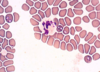

Trypanosoma equiperdum: Trypomastigotes

Trypomastigote in the blood